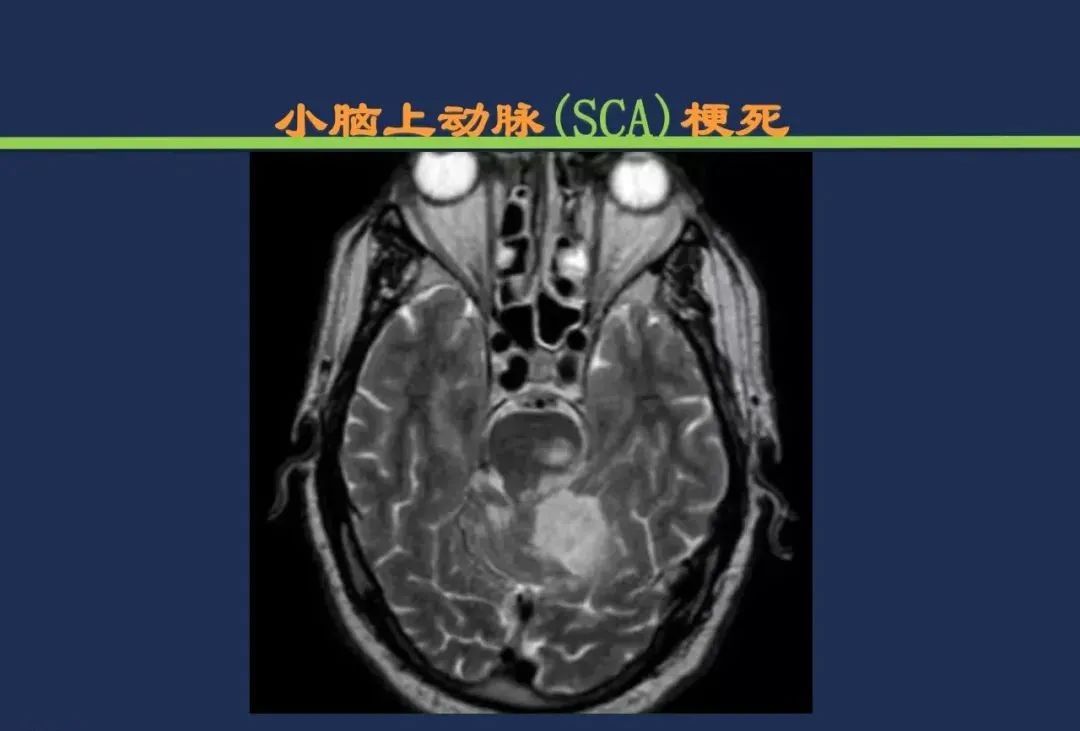

小脑前上动脉